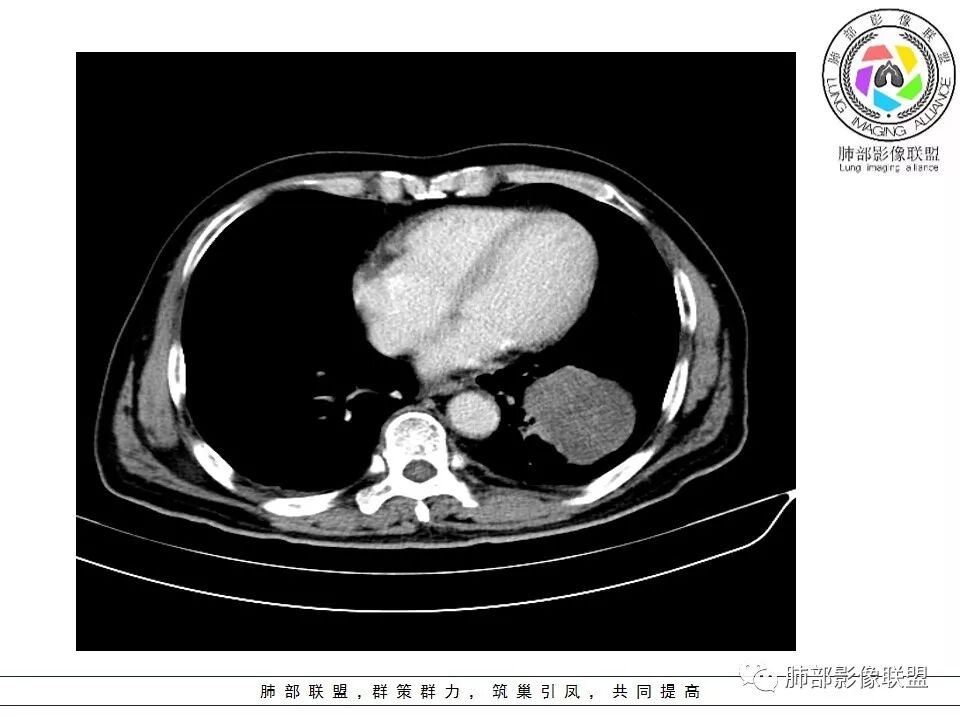

1.左肺下叶近肺门区肿块,肿块外围大,内带小,提示外围向中央生长,符合周围型SCLC沿支气管方向生长。

2.病灶边缘光滑,未见明显分叶、毛刺,符合神经内分泌癌、癌肉瘤及间叶来源肿瘤。

3.病灶内密度偏低,穿行血管未见明显异常,轻度不均匀强化,为乏血供病灶。病灶内可疑坏死区,未见空洞;乏血供符合SCLC,但坏死区不符合。

6.左肺门淋巴结肿大,与病灶局部融合分界不清,呈冰冻肺门;而纵隔内未见肿大淋巴结,冰冻肺门符合SCLC,但是病灶主体那么大,纵隔内没有明显肿大淋巴结,不是很符合SCLC娘小崽大的特点。

7.未见明显阻塞性炎症及阻塞性肺不张,更加提示病灶从外围向中央侵犯,符合SCLC罕见阻塞性肺不张。

病例小结

综上,影像学该病例符合肺内恶性,来源考虑神经内分泌癌、癌肉瘤或间叶来源肿瘤。老年男性,较大病灶伴有坏死,所以有群友考虑鳞癌、大细胞癌、癌肉瘤和肉瘤,但是鳞癌、癌肉瘤坏死常常合并空洞,而且像大细胞癌、癌肉瘤和肉瘤破坏力强,容易破坏血管;肉瘤一般不会引起肺门及纵隔的淋巴结肿大,所以肺门淋巴结肿大也不是很支持肉瘤。该病例部分征象支持小细胞癌(SCLC)的诊断。同病异影、异影同病都需要我们仔细甄别。